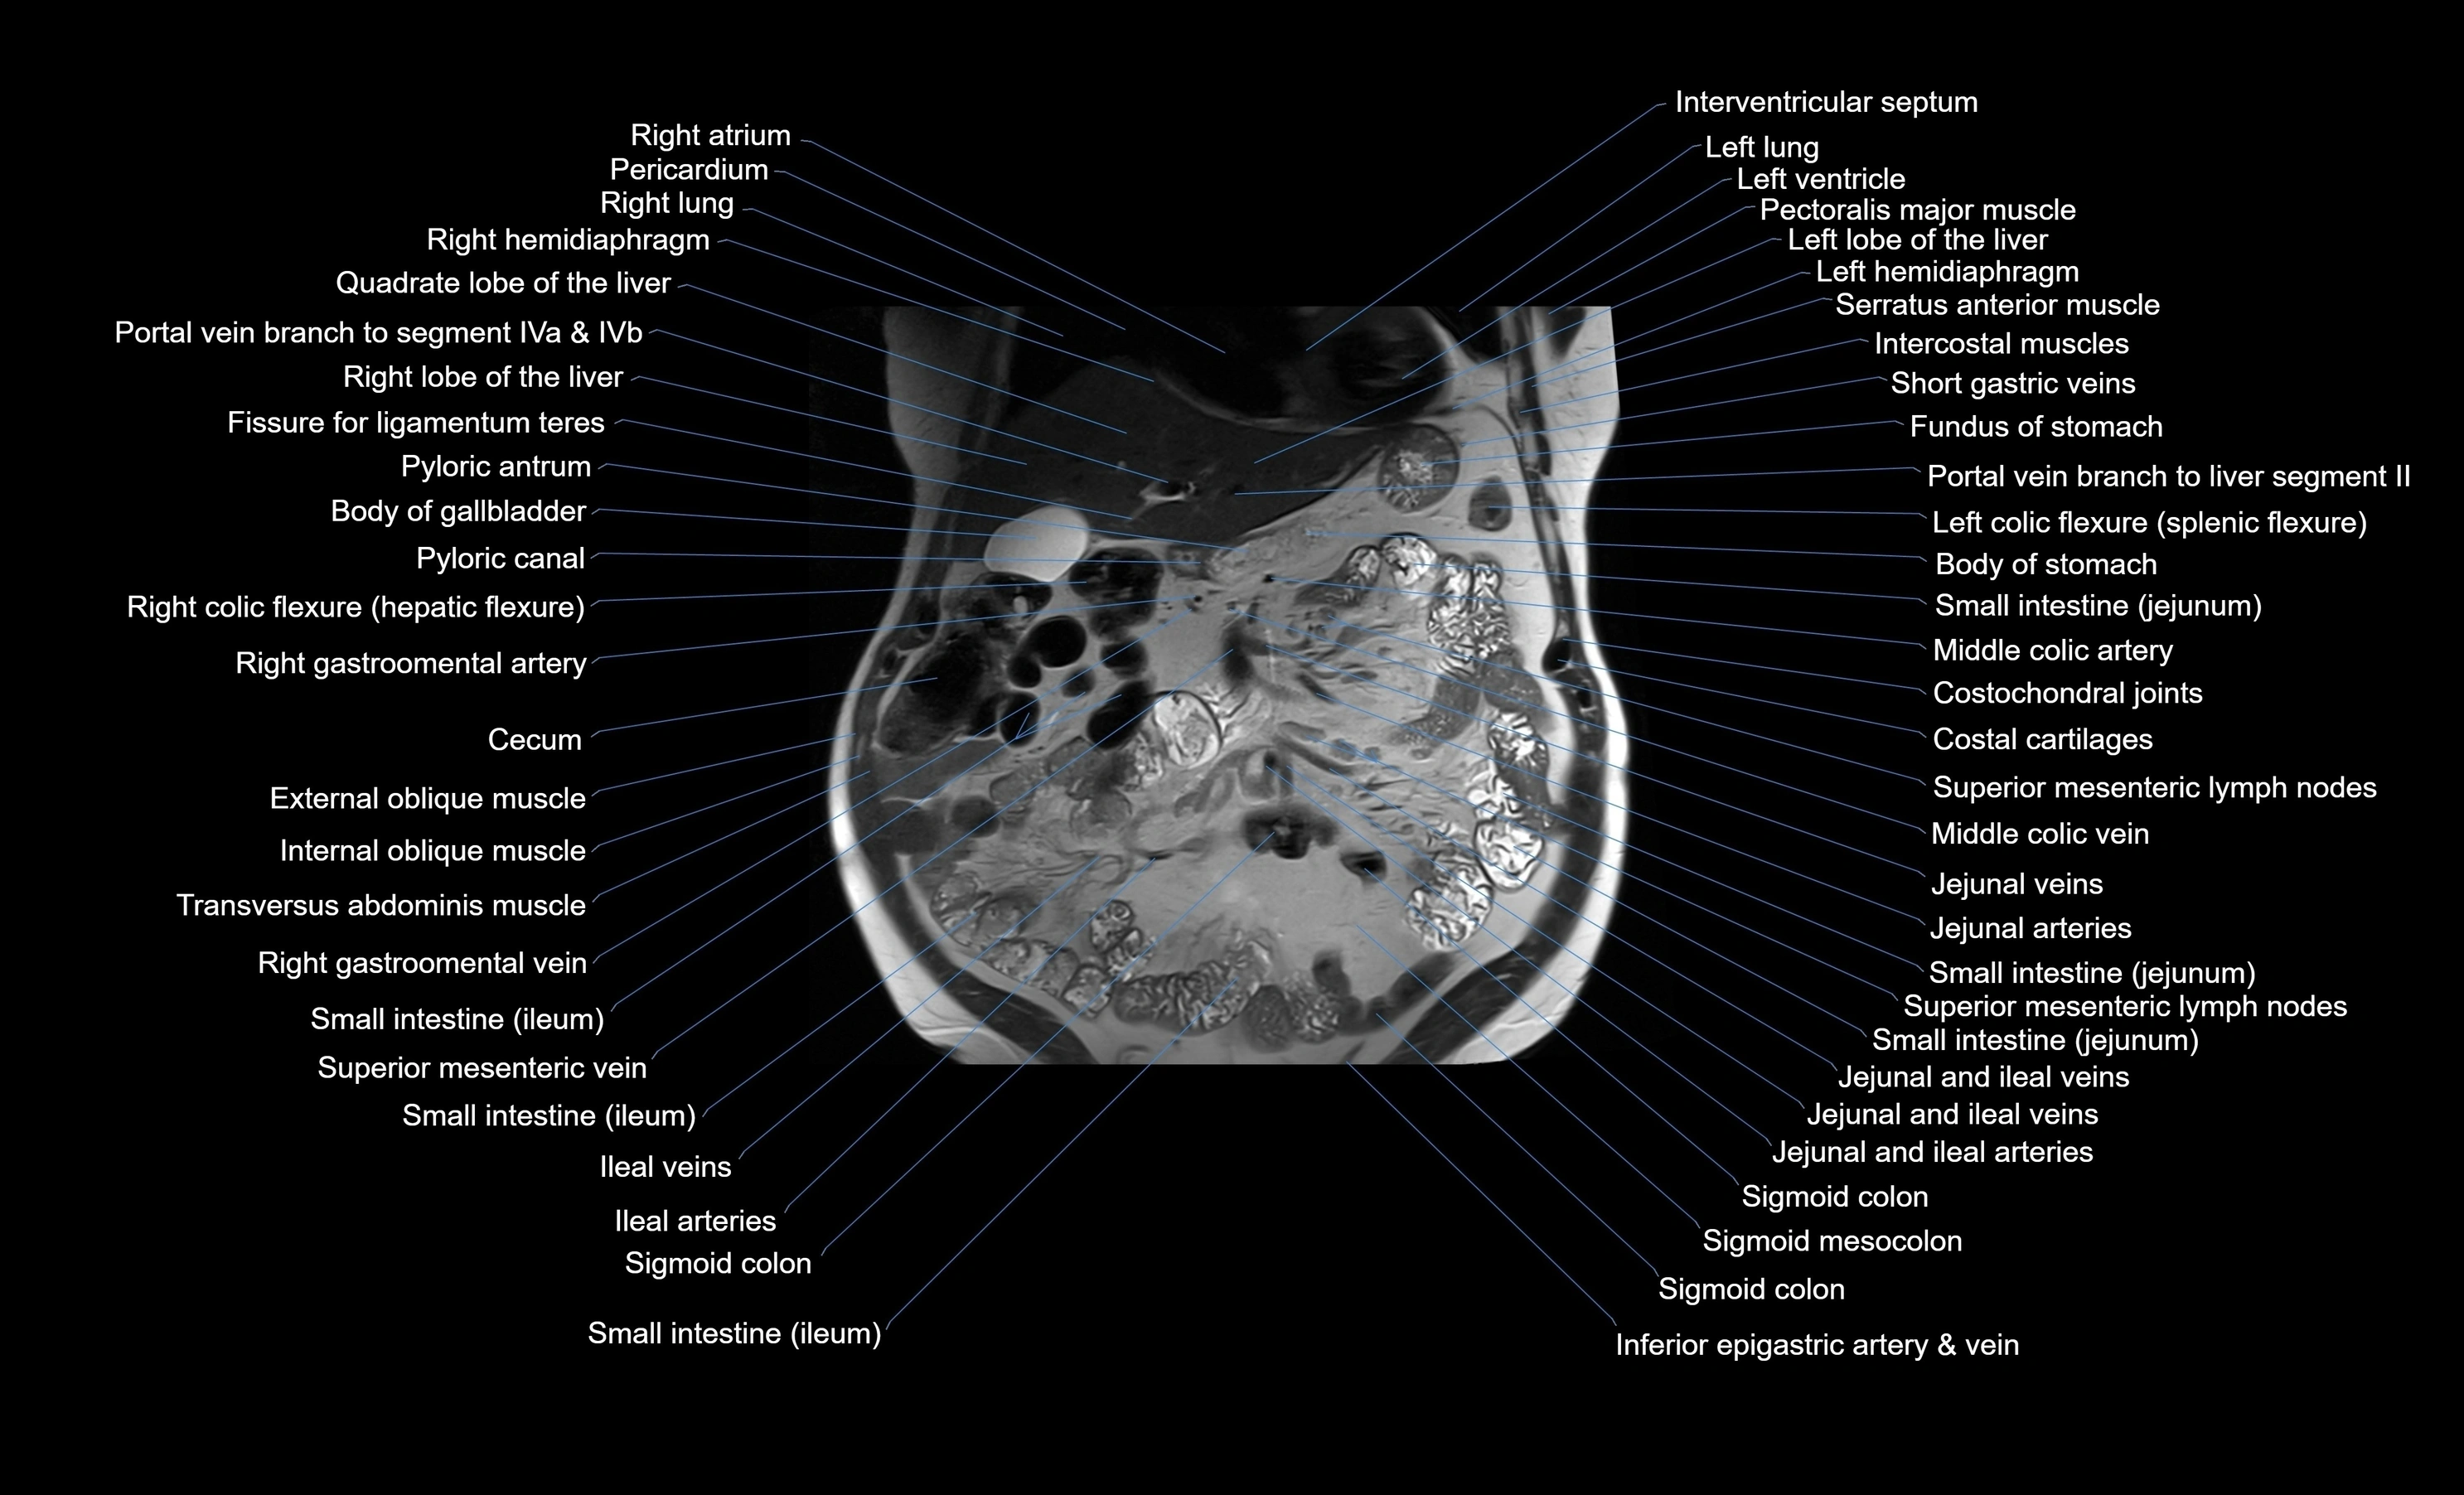

MRI images